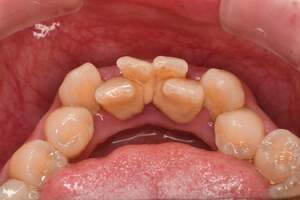

歯石除去

治療前1

治療後1

治療前2

治療後2

| 年齢 | 56歳・男性 |

| 主訴 | 主訴:歯石除去 治療部位:全顎 |

| 治療内容 | 初診検査・歯石除去 |

| 治療期間 | 60分 |

| 費用 | 合計約5,000円 初診検査約3,000〜4,000円 歯石除去約1,000円 (2024年4月現在) (歯の本数や検査内容で料金が変動します。) |

| リスク・副作用 | ・歯と歯の間に隙間ができるので、息が漏れ発音しにくいと感じることがあります。 ・歯ぐきの炎症がある場合は歯石除去中に出血を伴う可能性があります。 ・処置後に歯がしみることがあります。 ・歯ぐきの炎症が軽減すると歯ぐきが引き締まり、歯が長く見えることがあります。 |

| 治療方針 | 歯石除去・ブラッシング指導後SRP(歯ぐきの中に付着する歯石の除去) |

| 特記事項 | ・30年ぶりの歯科医院 ・毎食後の歯ブラシ習慣はあるが1分程度 |

| 担当者所見 | 全体の検査と歯石除去希望で来院されました。 特に下顎前歯部の歯と歯の間の歯石が、笑った時に見えてしまい気になるとのことで、初診検査後に歯石除去を行いました。 ブラッシング指導は歯間ブラシの入れ方と歯ブラシの動かし方をお伝えしました。 今後は治療と共に縁下歯石(歯ぐきの中に付着する歯石)の除去を行なっていく予定です。 |